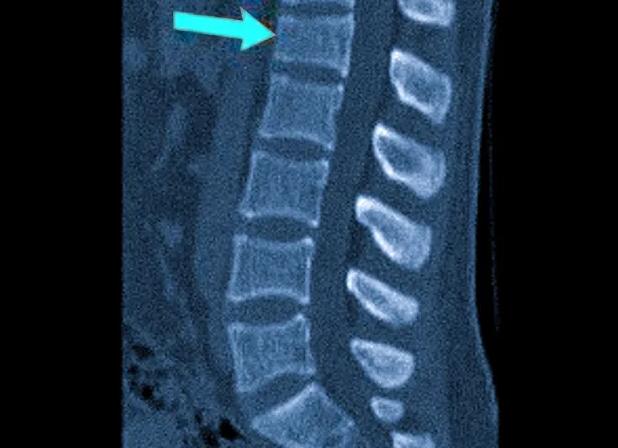

КТ позвоночника — подготовка, как делают и что показывает общее обследование